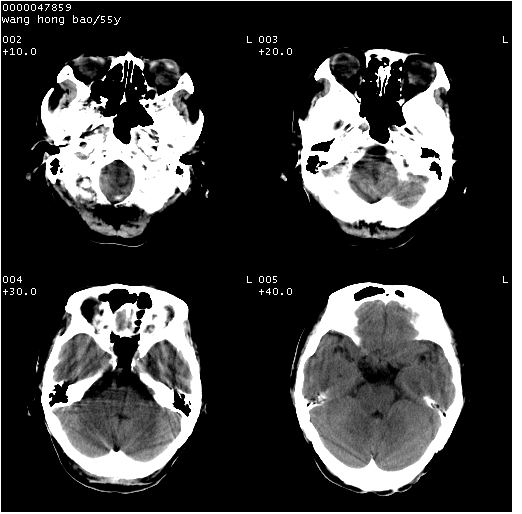

以下是引用dyqct在2008-5-3 23:36:00的发言:[br]桥前池区可疑蛛网膜囊肿。其它未见明显异常。建议做mri。

以下是引用qiushi在2008-5-4 10:10:00的发言:[br]鞍上池前缘突出影为双侧额叶直回;箭头所指为双侧正常之人字缝.[br]桥前池区可疑表皮样囊肿或蛛网膜囊肿,必要时mri

以下是引用zjzjr在2008-5-4 14:50:00的发言:[br]桥前池区可疑蛛网膜囊肿。其它未见明显异常。建议做mri。